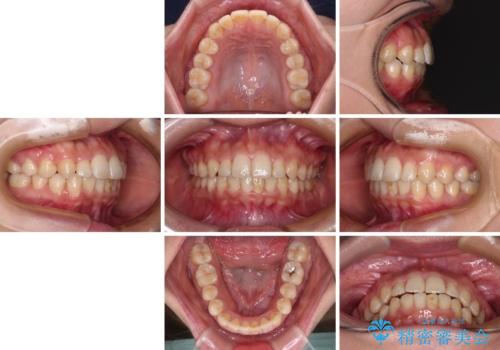

治療前にお伝えした治療期間は1~1年半でして、1年4か月の期間で終えることができました。

ワイヤー矯正は見た目や装置が当たることでの痛みを気にされる方が多いですが、月1回来院して処置をしてもらうだけで歯並びが整うため、大変お勧めです。